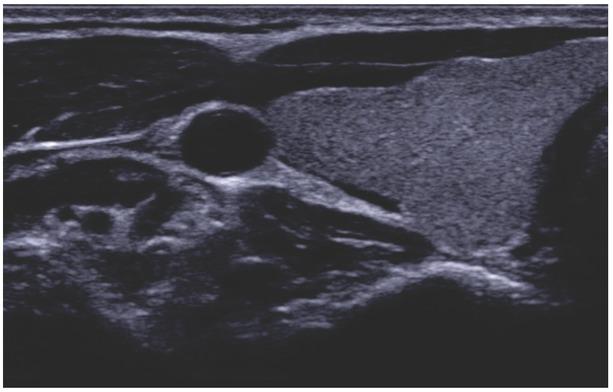

Fig. 1